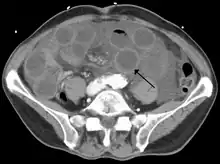

![]() | |

Computed tomography (CT) showing dilated loops of small bowel with thickened walls (black arrow), findings characteristic of ischemic bowel due to thrombosis of the superior mesenteric vein. | |